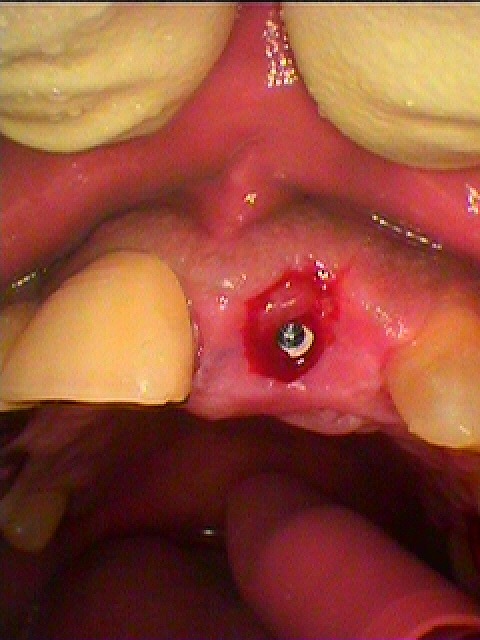

補填剤にて固めます。| |広島市安佐南区の歯科医院 補填剤にて固めます。 トップ お知らせ・ブログ 補填剤にて固めます。 補填剤にて固めます。 Web診療予約 初めての方へ 選ばれ続ける理由 院内設備について 歯が痛いしみる一般歯科 歯がぐらぐらする歯周病 健康な歯を保ちたい予防歯科 子供の虫歯予防をしたい小児歯科 銀歯をセラミックに審美歯科 白い歯を目指しませんか?ホワイトニング 矯正専門医がいるので安心矯正歯科 抜けた歯を補いたいインプラント・入れ歯 医院案内 スタッフ紹介 メリィハウス歯科クリニックオフィシャルホームページ ラベンダー歯科クリニックオフィシャルホームページ お知らせ・ブログ ホーム 診療科目 一般歯科 歯周病治療 予防治療 小児歯科 審美治療 ホワイトニング 矯正歯科 入れ歯・インプラント マウスピース矯正 初めての方へ 院長・スタッフ 設備紹介 医院案内・アクセス メニューを閉じる